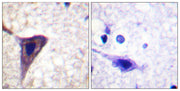

BID (phospho Ser78) rabbit pAb